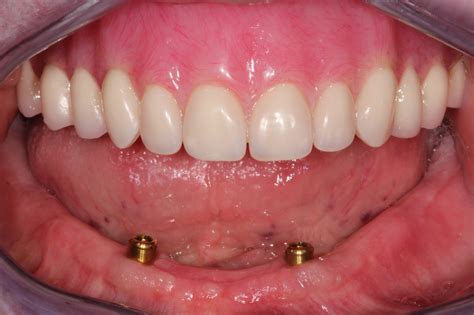

Over denture implants have revolutionized the field of dentistry, offering a stable and comfortable solution for individuals who have lost most or all of their teeth. This innovative procedure combines the benefits of traditional dentures with the stability and functionality of dental implants, providing a more secure and natural-feeling alternative. Over denture implants are designed to support a full or partial denture, ensuring that it stays firmly in place while eating, speaking, and smiling.

Over denture implants are a type of dental implant that supports a denture, providing a more secure fit compared to traditional dentures. These implants are surgically placed into the jawbone and act as anchors for the denture, preventing it from slipping or moving out of place. This stability enhances the overall comfort and functionality of the denture, allowing patients to enjoy their favorite foods and speak with confidence.

• Improved Stability: Over denture implants provide a secure fit, preventing the denture from slipping or moving out of place.

• Enhanced Comfort: The stability of over denture implants reduces irritation and discomfort often associated with traditional dentures.

• Improved Speech: The secure fit of over denture implants helps patients speak more clearly and confidently.

Once the implants have fully integrated with the jawbone, the dentist will attach the denture to the implants. For ball-retained implants, the dentist will place the ball-shaped attachments onto the implants and fit the denture with corresponding sockets. For bar-retained implants, the dentist will attach a thin metal bar to the implants and fit the denture with a corresponding attachment.